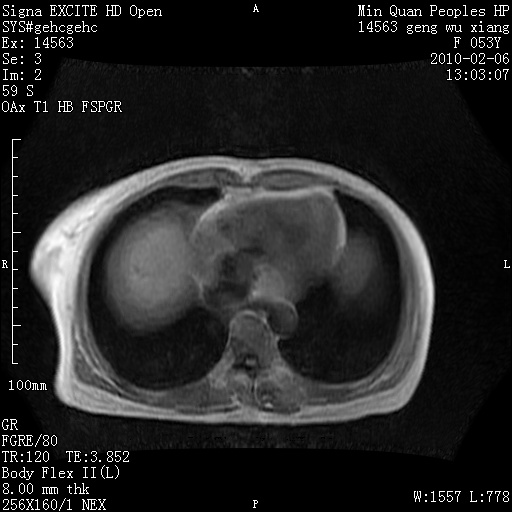

标题: MRI2762:胆道梗阻原因?

f,53y,全身黄染多日。

高位胆道梗阻 胆管癌可能性大

支持 高位胆道梗阻 胆管癌可能性大。